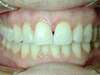

Vues avant le traitement